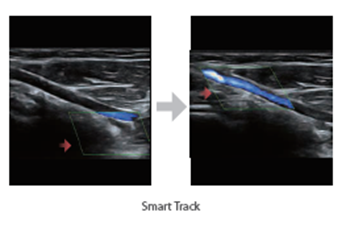

Ηχοβόλος κεφαλή τύπου Linear Array L13-3N από 3,0 MHz έως 13,0MHz MHz με δυνατότητα επιλογής διαφορετικών συχνοτήτων στο B-Mode, Doppler, Έγχρωμο Doppler για απεικόνιση σε εξετάσεις και εφαρμογές για μικρά όργανα, αγγεία, κοιλία, νεύρα, μαστό, θυροειδή κλπ.